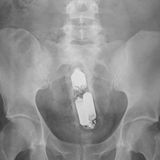

Diese Dinge gehören dort eigentlich nicht hin: Immer wieder passieren Unfälle, wenn Menschen sich zur sexuellen Stimulation über den After Gegenstände in den Darm einführen. Ob Orangen, Spraydosen oder Kaffeebüchsen - der Fantasie sind dabei offenbar keine Grenzen gesetzt.

Die Webseite radiopaedia.org zeigt, welche Dinge Ärzte auf Röntgenbildern schon entdeckt haben. Die Aufnahmen wirken skurril und erschreckend zugleich und machen deutlich, wie weit die eingeführten Dinge bereits in den mescnhlichen Darm vordringen können.

Aber Glück im Unglück für die Patienten: Die Gegenstände können meist ohne Operation entfernt werden. Sehen Sie hier einige der spektakulärsten Röntgenaufnahmen. Da runzeln selbst Chirurgen die Stirn.